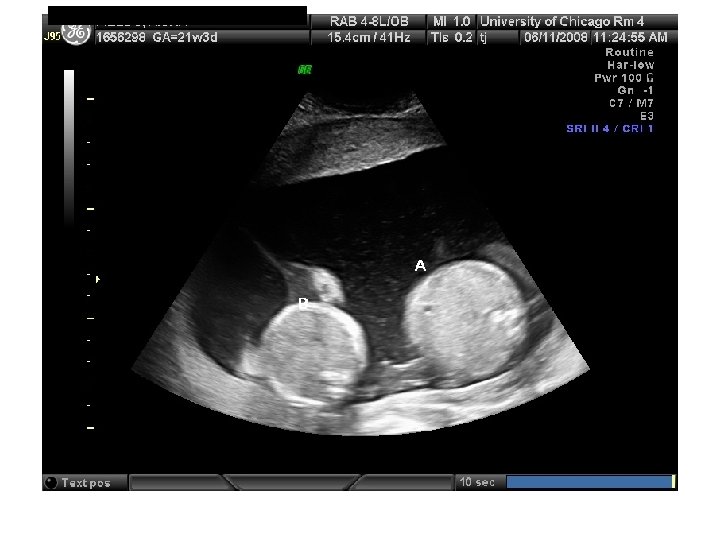

SCREENING OF MULTIPLE GESTATIONS FOR TRISOMY 21 • Maternal age: Detection same as singletons • Second-trimester serum: 45% detection in twins • NT: Detection same as singletons if dichorionic; false positive rate higher if monochorionic • NT+serum: 75% detection in twins with 9% false positives • Higher-order pregnancies: Only maternal age and NT are reliable

QUIZ What is Your Diagnosis? Case: Patient J. F. 30 years old, at 32 week gestation. Presented with the following pictures.

Answer: a) Trisomy 21 b) Non-immune Hydops c) Paravo virus Infection